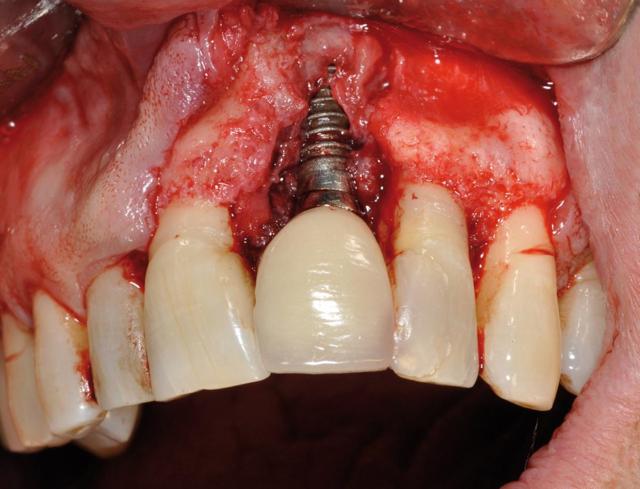

How long does it take for dental implants to fuse to bone?

Once the pillars are implanted in the jawbone, you must wait for the implant to connect to the bone. On the same subject : How to get health insurance to pay for dental implants. This process is known as osseointegration and usually takes about 4 to 6 months.

Why do implants have expiration dates?

This sterility should be maintained until the time of placement, which means that the “integrity” of the package must also be preserved through that period until the time of placement. Therefore, the expiration date of dental implants corresponds to the expiration date of the packaging integrity.